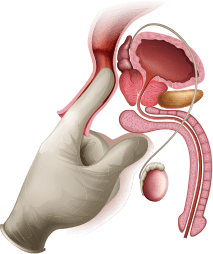

Prostatit - erkeklerin geliştiğini bilmeden

yıllarca yaşadığı bir hastalık,

adamı içeriden yok eder ve sağlığını, gücünü ve hatta hayatını tehdit eder

Prostatitin ana semptomu - idrara çıkma ihlali

idrara çıkma sırasında yanma

ve ağrı

eksik boşalma

hissi,

ağrılı

idrara çıkma

gece bir kereden

fazla tuvalete gitme

idrara çıktıktan sonra

idrar tahsisi

Diğer prostatit belirtileri:

-

üretra ve alt karın

bölgesinde ağrı -

seks yapma arzusu

eksikliği - zayıf ve sarkık ereksiyon

- ağrılı cinsel temas

- erken boşalma

-

39-40 ℃ ye kadar

artan vücut sıcaklığı.

En iyi ihtimalle, kronik prostatit geri dönüşümsüz iktidarsızlığa

ve kısırlığa yol açar

En kötü ihtimalle, hayati risk taşıyan ve uzun, ağrılı bir iyileşme süresi olan ciddi hastalıklar.

mesane obstrüksiyonu

mesane obstrüksiyonu

tekrarlayan sistit

tekrarlayan sistit

üretra daralması

üretra daralması

prostat apsesi

prostat apsesi

piyelonefrit

piyelonefrit

Sepsis

Sepsis